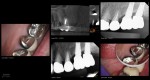

13 years on a tooth which shouldn’t have made it

Collage-2140635390-Page00